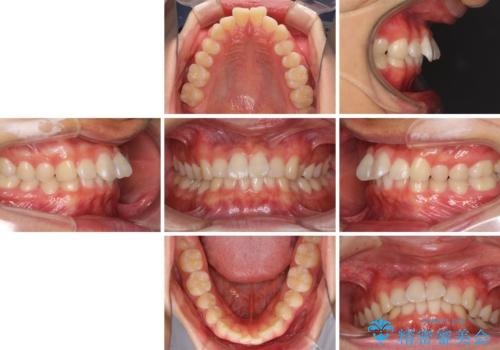

深い咬み合わせとデコボコ ワイヤー矯正で短期治療

- 前歯のデコボコを改善したいとのことで来院された患者様です。

インビザラインでの治療も可能でしたが、深い咬み合わせと奥歯の咬み合わせを改善するにあたり、ワイヤー矯正の方が治療期間を短縮できると判断し、ワイヤー矯正をお勧めしました。

結果として、1年かからずに奥歯の咬み合わせを改善することができました。